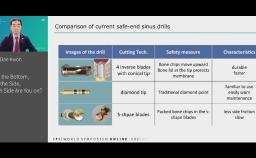

bone graft; sinus floor elevation; bone metabolism; dental implants